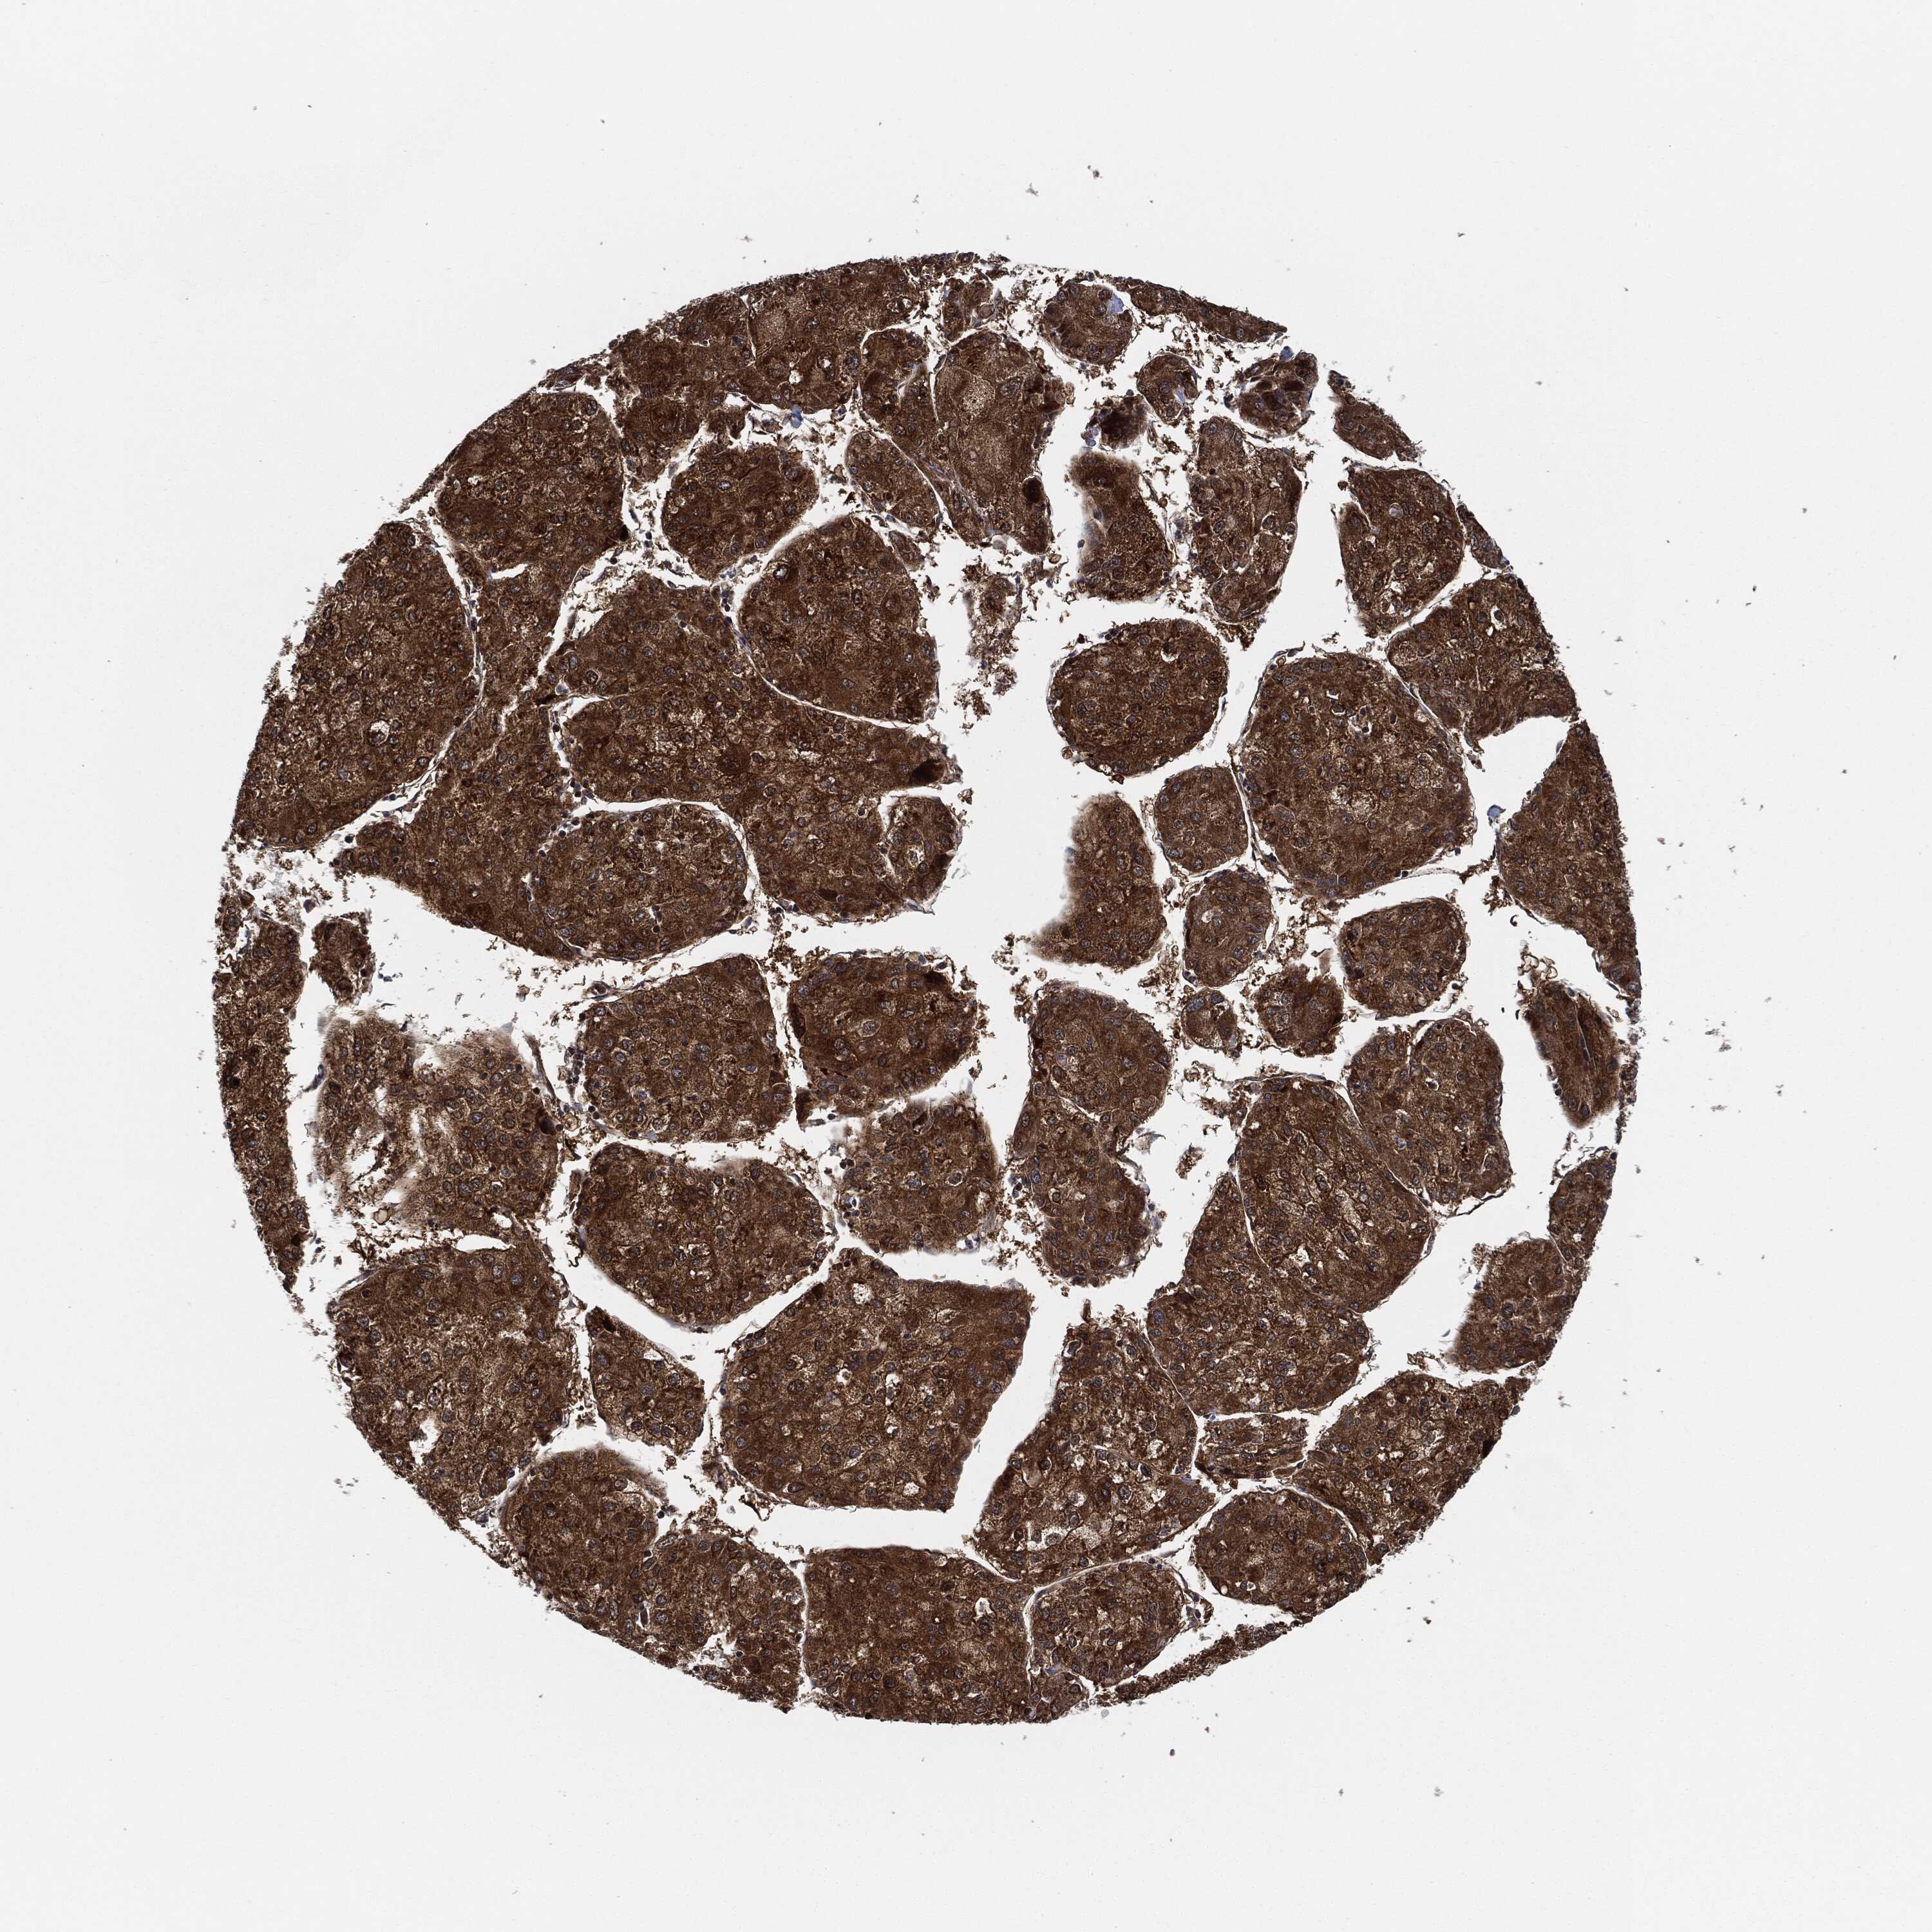

LIVER CANCER - Protein expressioni

A mouse-over function shows sample information and annotation data. Click on an image to view it in a full screen mode. Samples can be filtered based on level of antibody staining by selecting one or several of the following categories: high, medium, low and not detected. The assay and annotation is described here.

Note that samples used for immunohistochemistry by the Human Protein Atlas do not correspond to samples in the TCGA dataset.

Antibody stainingi

Antibody staining in the annotated cell types in the current human tissue is reported as not detected, low, medium, or high, based on conventional immunohistochemistry profiling in selected tissues. This score is based on the combination of the staining intensity and fraction of stained cells.

Each image is clickable and will lead to virtual microscopy that enables deeper exploration of all samples and also displays staining intensity scores, fraction scores and subcellular localization as well as patient and tissue information for each sample.

Antibody HPA002633

Antibody HPA046758

Antibody CAB010906

Staining

High

Medium

Low

Not detected

Intensity

Strong

Moderate

Weak

Negative

Quantity

>75%

75%-25%

<25%

None

Location

Nuclear

Cytoplasmic/membranous

Cytoplasmic/membranous,nuclear

Cholangiocarcinoma

Carcinoma, Hepatocellular, NOS